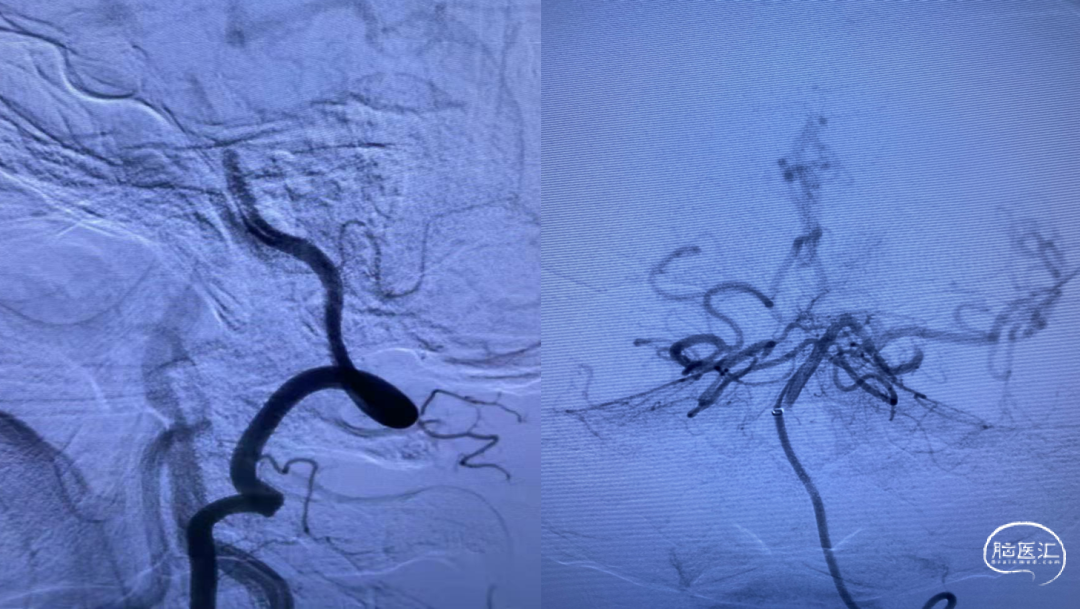

脑血管造影提示:左侧颈内动脉起始段重度狭窄,基底动脉尖闭塞,栓塞可能性大

微导丝引导ACE 68抽吸导管,将抽吸导管ACE 68送至基底动脉闭塞近端,接触血栓后并深入血栓2MM左右。

持续保持负压约2分钟后,持续负压抽吸下缓慢撤出抽吸导管,撤出抽吸导管过程中出现回血通畅。手推造影,见基底动脉显影良好,双侧大脑后动脉显影良好,双侧小脑上动脉显影良好,TICI 分级3级。